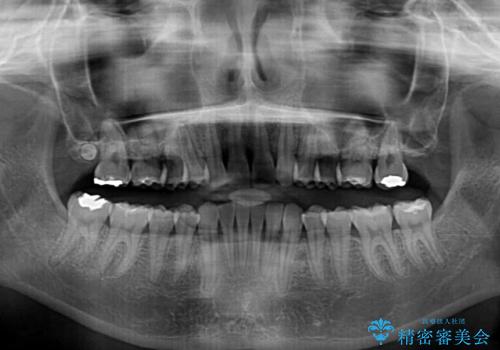

上顎前歯が2本欠損 インビザラインによる叢生の解消

- 深い咬み合わせと前歯のデコボコを気にして来院された患者様です。

上顎前歯2本が欠損しているため、妥協的なゴールを設定しインビザラインで矯正治療を行うこととしました。

上下前歯の大きさのアンバランスにより、深い咬み合わせと奥歯の咬みにくさがなかなか解決されず、治療に長期間を要することとなりました。